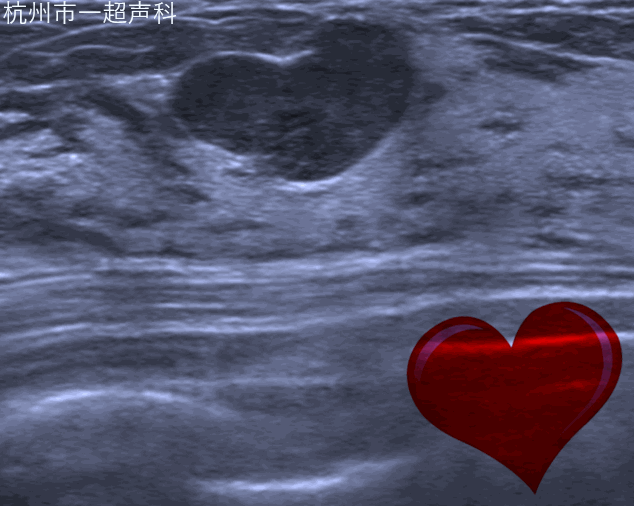

自动乳腺容积超声应用宽幅高频探头的自动扫描实现乳腺全容积的规范化图像,减少漏诊;独特的冠状面对鉴别诊断提供了三维的信息。自动乳腺容积超声对早期乳腺癌的影像学诊断,乳腺结节的BI-RADS分类评估,乳腺肿瘤的临床分期,新辅助化疗的疗效评估,乳腺癌的筛查有明显的优势。超声影像科于2010年在省内率先开展该项技术,也是国内最先开展的医院之一。目前无论在累积的病例数还是诊断水平均属国内领先。2018年,我们完成30000例病人的基础上在国内发布首个自动乳腺全容积成像系统操作流程,为行业制订检查规范。团队发表包括SCI在内成人抖音相关的文章40余篇,在RSNA及WFUMB等国际会议发表研究结果,开展全国的多中心研究,与知名院校的产学研合作。每年举办国际级继续教育学习班,作为培训基地,为全国各大医院培训医生200余人。加强国际交流,每年接待来自欧美、亚太地区的专家进行学术交流与合作。